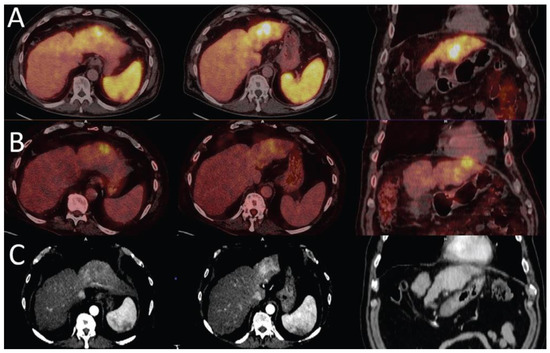

- Hartenbach, M.; Weber, S.; Albert, N.L.; Hartenbach, S.; Hirtl, A.; Zacherl, M.J.; Paprottka, P.M.; Tiling, R.; Bartenstein, P.; Hacker, M.; et al. Evaluating Treatment Response of Radioembolization in Intermediate-Stage Hepatocellular Carcinoma Patients Using <sup>18</sup>F-Fluoroethylcholine PET/CT. J. Nucl. Med. 2015, 56, 1661–1666. [Google Scholar] [CrossRef]

- Reizine, E.; Chalaye, J.; Mule, S.; Regnault, H.; Perrin, C.; Calderaro, J.; Laurent, A.; Amaddeo, G.; Kobeiter, H.; Tacher, V. Utility of Early Posttreatment PET/CT Evaluation Using FDG or 18F-FCH to Predict Response to 90Y Radioembolization in Patients With Hepatocellular Carcinoma. Am. J. Roentgenol. 2022, 218, 359–369. [Google Scholar] [CrossRef] [PubMed]

- Filippi, L.; Bagni, O.; Notarianni, E.; Saltarelli, A.; Ambrogi, C.; Schillaci, O. PET/CT with 18F-choline or 18F-FDG in Hepatocellular Carcinoma Submitted to 90Y-TARE: A Real-World Study. Biomedicines 2022, 10, 2996. [Google Scholar] [CrossRef] [PubMed]